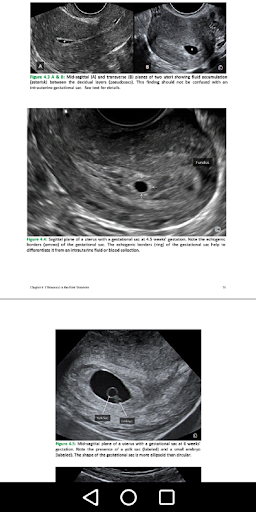

There are 1,234 illustrations and sonograms demonstrate clinical anatomy, patient positions, scanning techniques, normal and abnormal findings, and key principles.